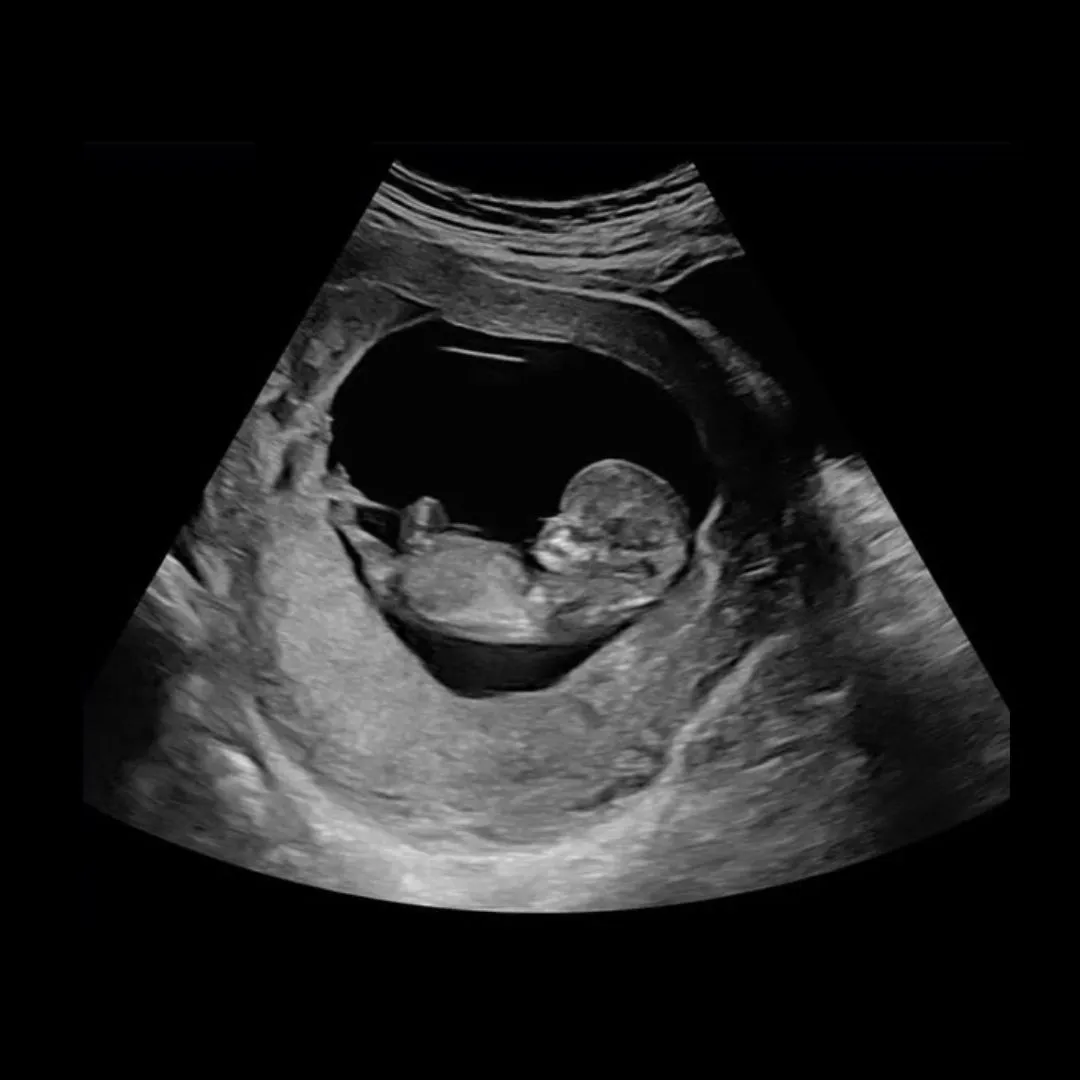

Ujian DNA tidak dijalankan semasa bayi dalam perut…Risau risiko lain

Seiring perkembangan siasatan, polis menahan 13 lagi individu yang dipercayai mempunyai kaitan dengan kehamilan tersebut. Bagi mendapatkan pengesahan lebih tepat, ujian DNA dijalankan selepas remaja itu selamat melahirkan bayi, memandangkan pengambilan sampel tidak dapat dilakukan ketika kandungan masih dalam rahim atas faktor keselamatan.